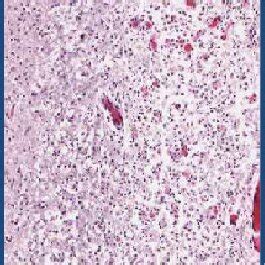

In addition to the information above, here is a curated collection of images related to A Photomicrograph Of H E Stained Section In The Left Hippocampus From.

- Photomicrograph Of H&e-stained Hippocampus, Cerebellum, And Brain ...